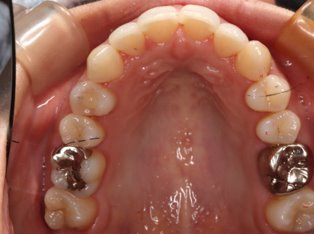

治療前

治療終了前